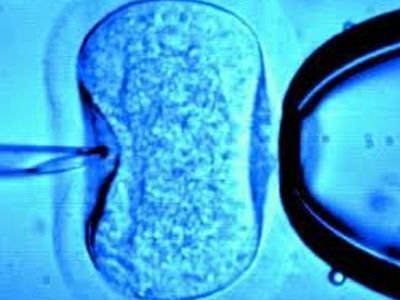

Πρόγνωση επιτυχούς εξωσωματικής γονιμοποίησης

Πολλά ζευγάρια που επιθυμούν διακαώς να αποκτήσουν παιδιά αλλά αντιμετωπίζουν δυσκολίες, έχουν δοκιμάσει την μέθοδο IVF, αυτή δηλαδή της εξωσωματικής γονιμοποίησης. Ακόμη κι έτσι, όμως, οι πιθανότητες σύλληψης δεν ξεπερνούν το 30%.

Οι ερευνητές, όμως, του Stanford University δεν σταμάτησαν εκεί: ανακάλυψαν μια μέθοδο, που βοηθά στον εντοπισμό του πιο «δυνατού» εμβρύου, το οποίο θα οδηγεί με περισσότερες πιθανότητες σε εγκυμοσύνη και επιτυχή τοκετό. Καταγράφοντας κάθε στάδιο εξέλιξης του εμβρύου από την στιγμή της γονιμοποίησης, οι ερευνητές ανακάλυψαν πως η χρονική διάρκεια που χρειάζεται ένα γονιμοποιημένο ωάριο για να διπλασιαστεί καθορίζει και τις πιθανότητες εξέλιξης σε ένα υγιές βρέφος.